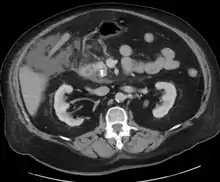

For imaging, abdominal ultrasound is convenient, simple, non-invasive, and inexpensive.[32] It is more sensitive and specific for pancreatitis from gallstones than other imaging modalities.[30] However, in 25–35% of patients the view of the pancreas can be obstructed by bowel gas making it difficult to evaluate.[29]

A contrast-enhanced CT scan is usually performed more than 48 hours after the onset of pain to evaluate for pancreatic necrosis and extrapancreatic fluid as well as predict the severity of the disease. CT scanning earlier can be falsely reassuring.